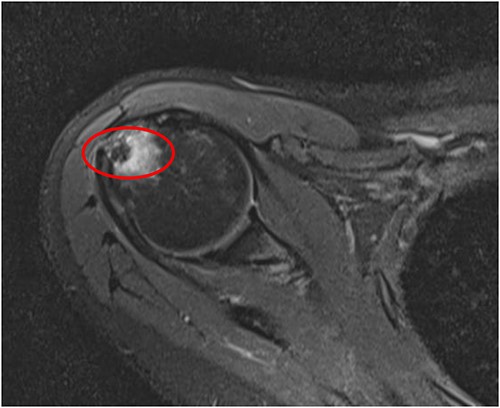

An MRI of the right shoulder showed calcifications over the supraspinatus tendon with an intraosseous lesion mimicking an aggressive or benign skeletal neoplasm (see Figs 2 and 3).

Coronal T2 image of right shoulder showing hypointense lesion; note: the red circle indicates the intraosseous extension of calcified deposits originating from calcified supraspinatus tendon, with surrounding marrow edema.